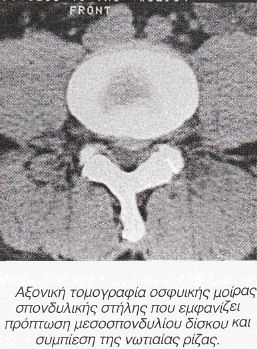

Ο ασθενής Κ.Α., 48 ετών, προσήλθε στις 29/1/92 πάσχων από Οσφυοϊσχυαλγία αριστερά, χρονολογούμενη από 10ετίας, αλλά με σοβαρή επιδείνωση τα 3 τελευταία χρόνια. Η κλινική διάγνωση επιβεβαιώνεται από αξονική τομογραφία της οσφυϊκής μοίρας της σπονδυλικής στήλης (114/10/89), όπου αναφέρεται: «Απεικονίζεται οπίσθια και αριστερά πλαγία πρόπτωση του μεσοσπονδυλίου δίσκου στο διάστημα 04-05. Ο δίσκος προκαλεί συμπίεση του νωτιαίου σάκκου, προβάλλει δε στην περιοχή του μεσοσπονδυλίου τρήματος και συμπιέζει τη σύστοιχο νωτιαία ρίζα. Μικρότερου βαθμού οπίσθια κεντρική πρόπτωση του μεσοσπονδυλίου δίσκου υπάρχει στο διάστημα 05-11». Η κλινική εικόνα είναι αρκετά σοβαρή.